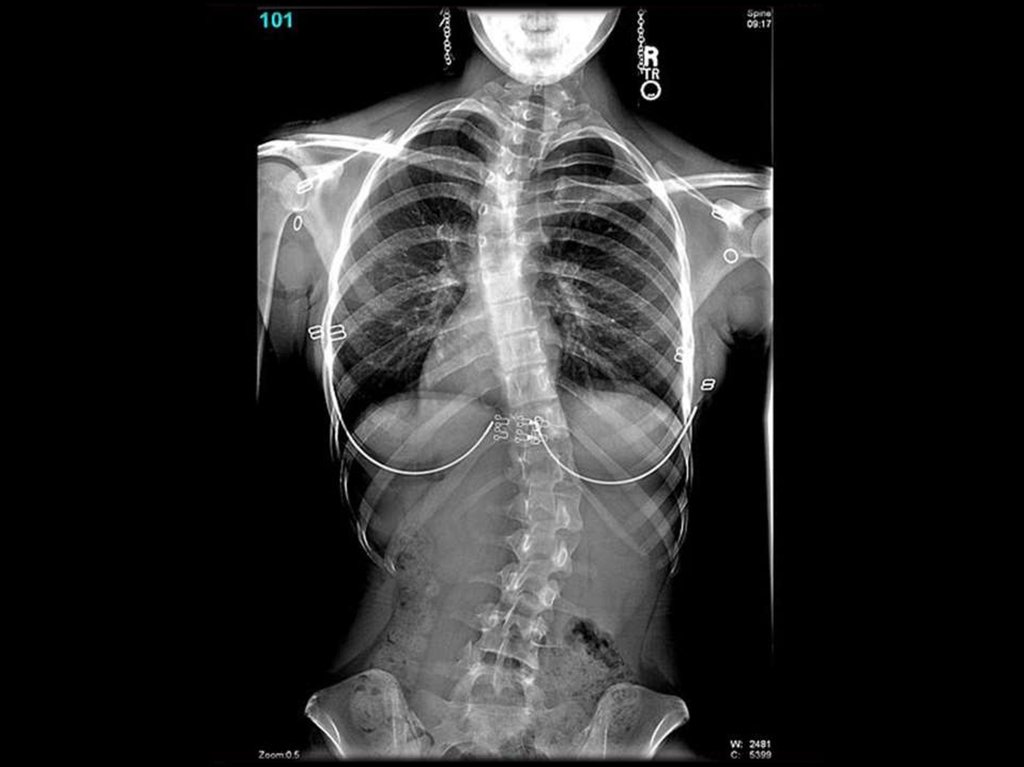

СКОЛЕОЗ ГРУДНОГО ОТДЕЛА